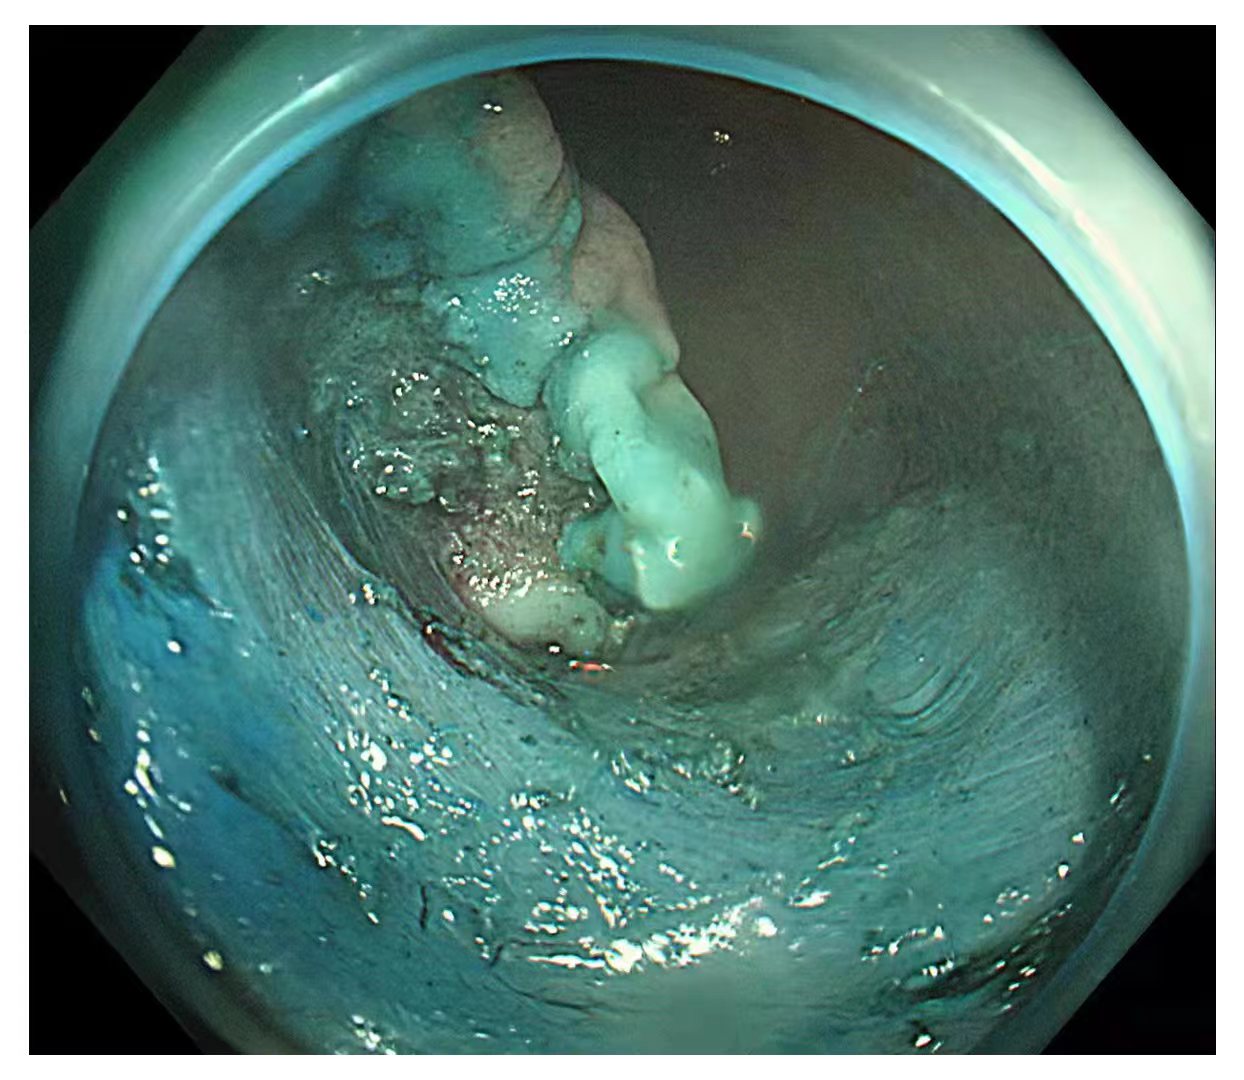

内镜中心在胃镜检查、结肠镜检查、息肉治疗、取除异物、超声内镜检查和食管支架术、内镜下黏膜剥离术等方面开展了大量的工作,结肠的回肠末端到达率98%,结肠息肉检出率达35%,早癌检出率1.5%。

内镜中心独立完成了多例食管、胃、结肠早癌完整切除术,并成功开展了食管良性狭窄切开术,间质瘤挖除术,食管癌伴食管狭窄支架置入术,消化道异物取出术,痔疮Ⅱ度以内的硬化术等。